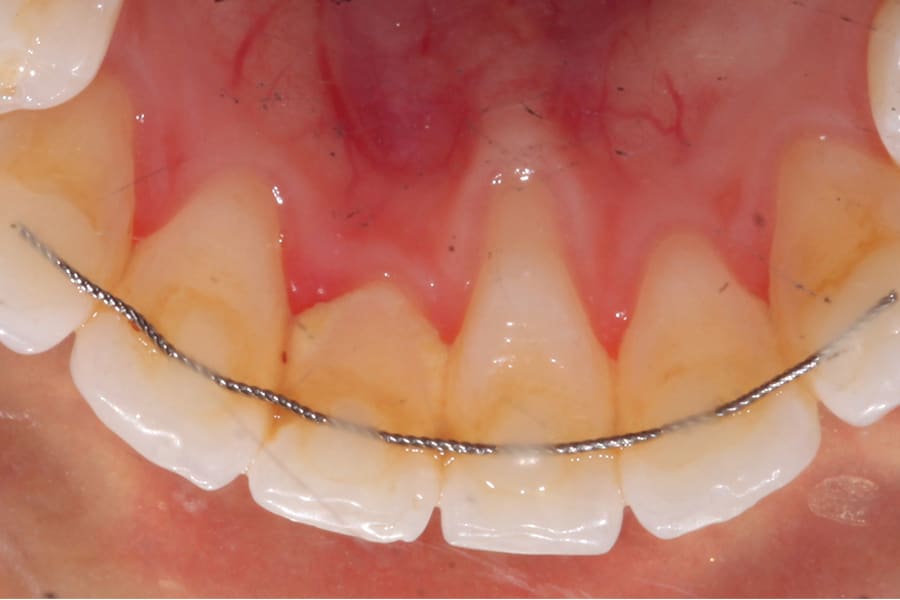

Obviously, more suitable and reliable fixed lingual retention designs are needed, and, fortunately, many are available. As described above, the twisted chairside fabricated design can be unreliable. A well-suited alternative is a passive braided design as shown in Figure 2 (Ortho FlexTech® stainless steel, Reliance Orthodontics, relianceorthodontics.com). The braided design does not uncoil over time. The lingual retainer is placed in passive fashion after being cut to the proper length from a spool and bonded to the appropriate teeth. This relatively inexpensive alternative is fabricated chairside with no laboratory intervention or special preparation required. One potential downside is that it is a relatively bulky option.